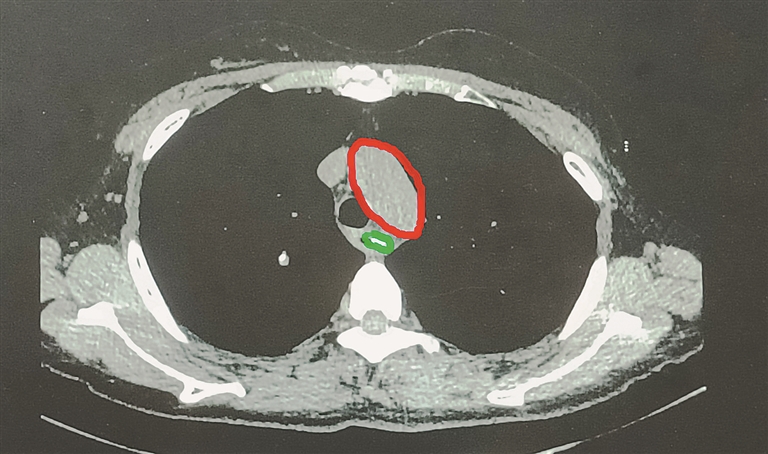

据介绍,纵隔CT可见枣核距离主动脉弓非常近,距离仅约5mm左右,一旦枣核穿破食道刺入主动脉弓就会造成患者大出血,甚至死亡。由于情况紧急,周一楠及路越医生当即联系了消化内科主任史立军,在史主任的指挥下,消化内科护士长马丽和内镜医生尹逊海、内镜护士季秀英,立即从家赶往医院,做好随时行急诊内镜治疗的准备。

“当时,枣核距离大血管距离极近,胃镜下异物取出术的风险极高。”据消化内科护士长马丽介绍,从陆阿姨进入病房到接受内镜治疗仅用了短短15分钟。